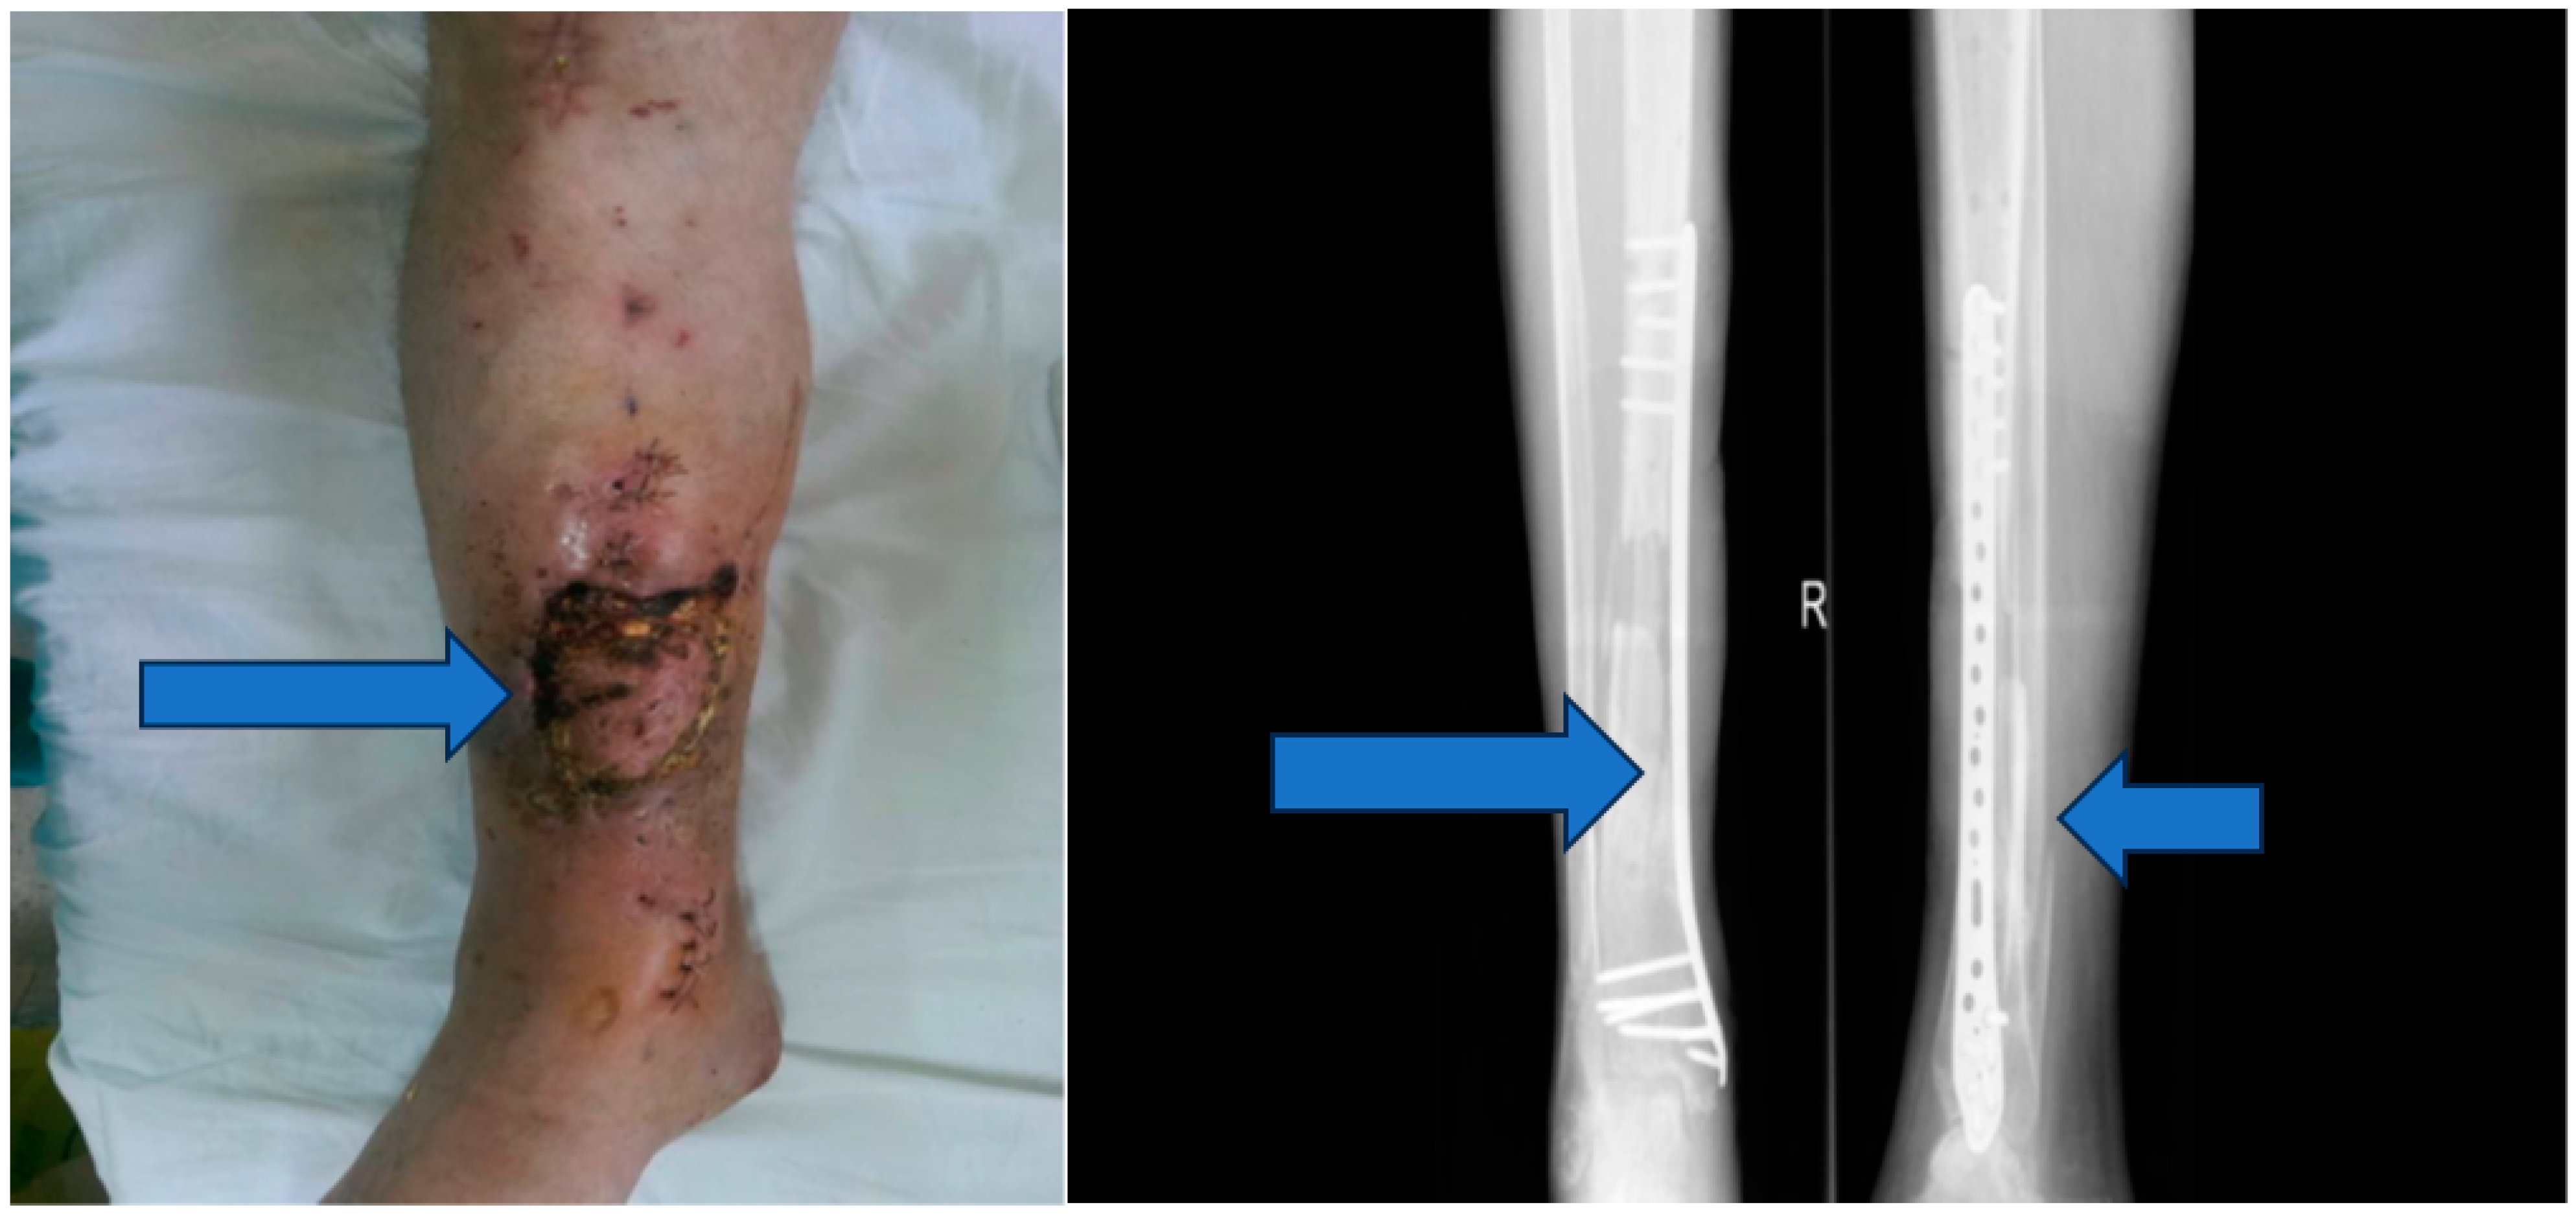

Stage 2: Infection control and debridement (Figure 4).

Objective: To address complications, prevent infection, and manage the wound dehiscence.

Methods: Implants from the initial surgery were removed, wide excisional debridement of necrotic tissue was carried out, pulse lavage was performed for wound cleansing, and osteoclasia was executed to facilitate bone healing. The peroneal malleolus was also manipulated, and a monoplane external fixation system was applied. Post-operatively, aspiration therapy using a vacuum pump was employed, and antibiotic therapy with vancomycin (2 g/day) for ten days was initiated based on the results of the antibiogram.

Figure 4. Vacuum pump and ex fix.

Jpm 13 01651 g004

Figure 5. Osteo-muscular defect.

Jpm 13 01651 g005